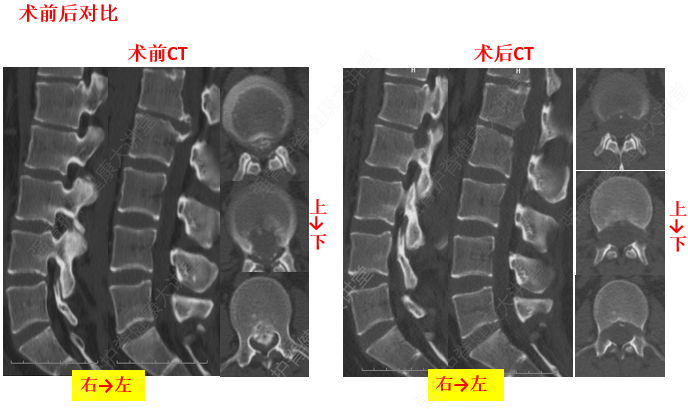

5、頸椎骨折

頸椎骨折

由于頸椎骨折,可造成出血,水腫,或碎骨片移位波及到椎間孔或椎管,直接壓迫頸神經(jīng)根或頸脊髓。骨癡的形成,使椎管、椎間孔發(fā)生狹窄性改變,產(chǎn)生脊髓、神經(jīng)根的受壓癥狀。